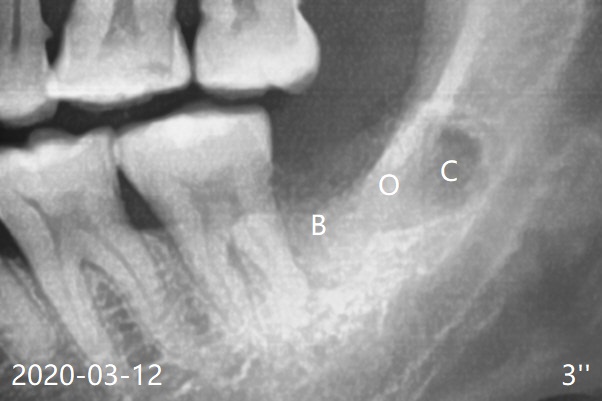

The bone distal to #18 is lost severely (Fig.1).  After #17 extraction and granulation tissue removal, Collagen Plug (Fig.3'' C), Osteogen Plug (O) and cortical/cancellous (50/50) mineralized allograft (.5-1 mm) saturated with ~ .2 ml of .3 mg/ml of rhPDGF-BB (B, one component of GEM21S) is placed in the socket.